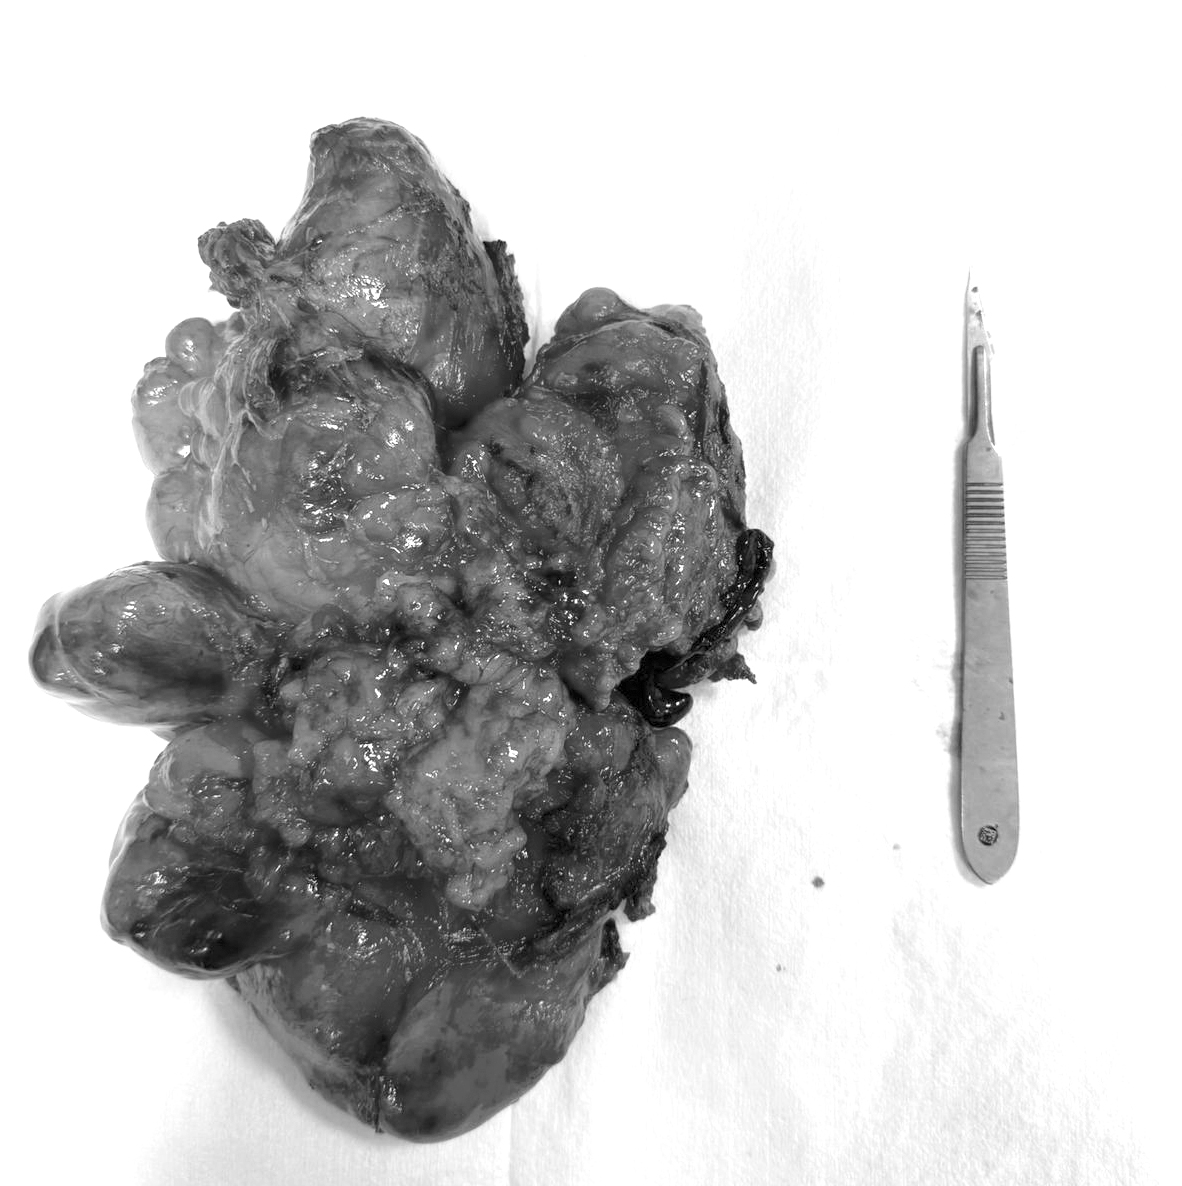

Durante la operación, los médicos encontraron un tumor de unos 20 centímetros de largo y 10 de diámetro. Era de forma irregular y bordes poco definidos. Estaba ubicado en la parte lateral del cuello, entre los músculos escalenos, pegado a la vena yugular interna con afectación de la vértebra cervical 7 y torácica 1 con invasión del canal medular. Además, llegaba hasta el tórax, cerca de la tráquea, y estaba firmemente adherido al plexo braquial derecho.

El objetivo fue extirpar todo el tumor, aliviar el dolor y mejorar la calidad de vida de la paciente.